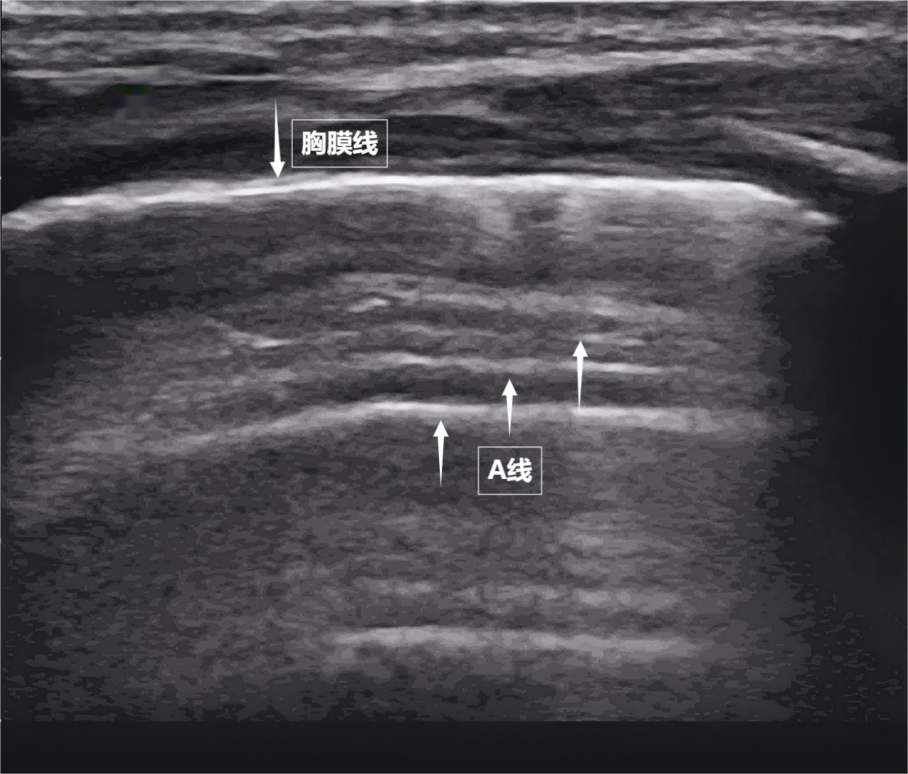

当声波穿过胸壁肋骨缝隙,首先会遇到紧贴肺表面的光滑薄膜——壁层胸膜和脏层胸膜。两者紧密相贴,中间没有多余的气体或液体。它们在屏幕上呈现为一条明亮、光滑的水平线,共同构成了胸膜线。这条线就是肺的"海岸线"。在它的下方,由于肺泡内大量气体对声波的强烈反射,会出现一系列与胸膜线平行的、等间距的、重复出现的明亮平行线,像海浪般不断向屏幕深处延伸,这就是A线( 见下图 )。A线是正常含气肺部的典型标志。它的存在直接提示肺表面含气充足,胸膜腔内无异常积液或气体。

图为正常新生儿肺部超声表现